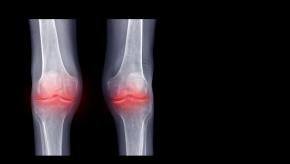

Pain Reduction with Methotrexate in Knee Osteoarthritis

The Annals of Internal Medicine reports that oral, low dose, weekly methotrexate significantly reduced knee osteoarthritis (KOA) pain, stiffness, and function in a randomized controlled trial.